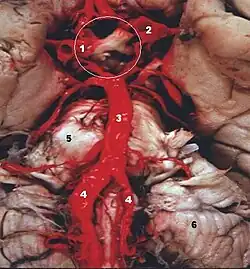

Las dos arterias vertebrales y la arteria basilar proporcionan sangre a la parte posterior del círculo arterial cerebral y se anastomosa con la parte anterior del círculo, irrigado por las arterias carótidas.

La dinámica de la sangre arterial en el sistema Vertebral-Basilar, depende de la interacción entre la entrada y la salida del flujo sanguíneo. Las arterias vertebrales determinan el flujo convergente de entrada y las arterias cerebelosa superior y cerebral posterior determinan el flujo divergente de salida de este sistema.[5]